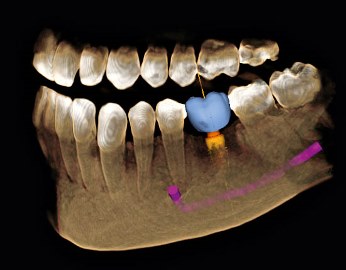

Das Digitale Volumentomogramm - DVT - ist eines der modernsten Hilfsmittel zur genauen räumlichen Darstellung und Vermessung eines Kiefers. Es wird z.B. bei der Planung von Implantaten, der Beurteilung des Zahnbettes, der Kiefergelenke oder vor chirurgischen Eingriffen angewendet. Das DVT liefert in vielen Fällen ein besseres Ergenis als die herkömmliche Röntgentechnik.

Die grundlegenden Vorteile des DVTs gegenüber dem "normalen" Röntgenbild sind:

- Maßstabgetreue Darstellung (Strecken und Winkel können exakt vermessen werden)

- Beurteilung der Knochenqualität (z.B. Knochenhärte) anhand der Dichtemessung

- Die Möglichkeit, DVT Bilddaten am Computer auszuwerten und mit dem Patienten bzw. Mitbehandler zu besprechen.

- Die Möglichkeit, Planungs- und Bohrschablonen aufgrund der DVT-Daten anzufertigen, um während der Operation gezielt und minimal invasiv die Implantate wie vorhergeplant zu setzen.

- Die Möglichkeit, Kunststoffmodelle und Schablonen im Maßstab 1:1 herzustellen, um damit Eingriffe exakt und risikominimiert zu planen und durchzuführen